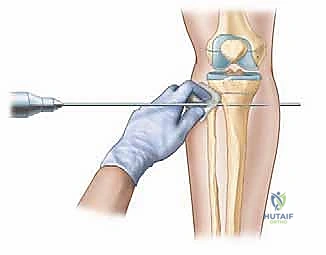

1. القطع العظمي القشري (Corticotomy): يقوم الجراح بقطع الطبقة الخارجية الصلبة للعظم مع الحفاظ التام على السمحاق (الغشاء المغلف للعظم) ونخاع العظم الداخلي، حيث تتركز الخلايا الجذعية والتروية الدموية.

2. يوم الجراحة: الدقة المتناهية

تحت التخدير المناسب، يقوم الدكتور هطيف بتركيب الجهاز (سواء الحلقات أو السكة الجانبية) بدقة بالغة مع مراعاة مسار الأعصاب والأوعية الدموية (وهنا تبرز أهمية خبرته في الجراحة الميكروسكوبية). بعد التثبيت، يتم إجراء القطع العظمي (Corticotomy) من خلال شق جراحي صغير جداً للحفاظ على التروية الدموية الحيوية.